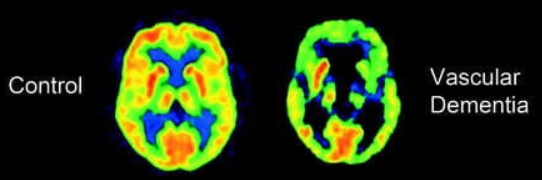

Dementie - Vasculaire dementie

problemen bloedvoorziening in hersenen → afsterven cellen witte stof

beperkingen mogen niet samenhangen met lichamelijke beperkingen

vaak plots

trager denken

goed bewustzijn van problemen